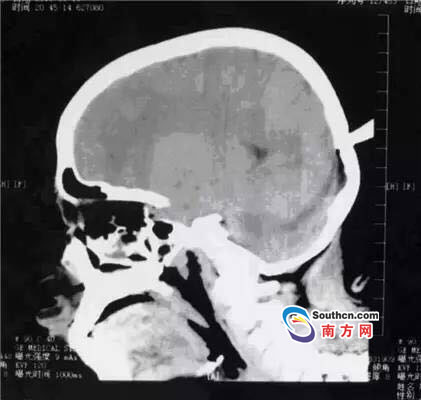

接到小玲受傷的消息,東莞市第三人民醫(yī)院急診科立即啟動了急癥危重患者搶救流程。急癥頭部CT顯示,飛鏢已穿透小玲的顱骨,并突破硬腦膜,情況非常兇險,小玲命懸一線。

此時,小玲也處于極度恐懼和不安中。醫(yī)生表示,必須及時手術(shù)取出異物、止血并妥善處理顱內(nèi)相關(guān)損傷,否則飛鏢將進(jìn)一步損傷腦組織,引起二次傷害,甚至可能引發(fā)顱內(nèi)大出血。搶救刻不容緩,醫(yī)院神經(jīng)外科醫(yī)師立即與麻醉手術(shù)科聯(lián)系,開通綠色通道準(zhǔn)備急診手術(shù)。

開顱還是不開顱?這是擺在神經(jīng)外科醫(yī)生面前最重要的問題。此時的檢查結(jié)果無法判斷有無血管和腦組織的損傷,開顱手術(shù)可以直接看到損傷的情況,及時進(jìn)行處理,但是如果飛鏢沒有損傷大血管,開顱的話就會造成比較大的創(chuàng)傷;不開顱手術(shù),手術(shù)的全過程造成的損傷就會減少,但是如果有大血管的損傷,不開顱直接拔出飛鏢,就不能及時進(jìn)行止血和清創(chuàng)。

兩種選擇都是機(jī)會與風(fēng)險并存的,最后神經(jīng)外科通過會診,在充分征求家屬意見的基礎(chǔ)上,決定進(jìn)行不開顱手術(shù),同時,也充分考慮手術(shù)風(fēng)險,做好開顱手術(shù)的一切準(zhǔn)備。